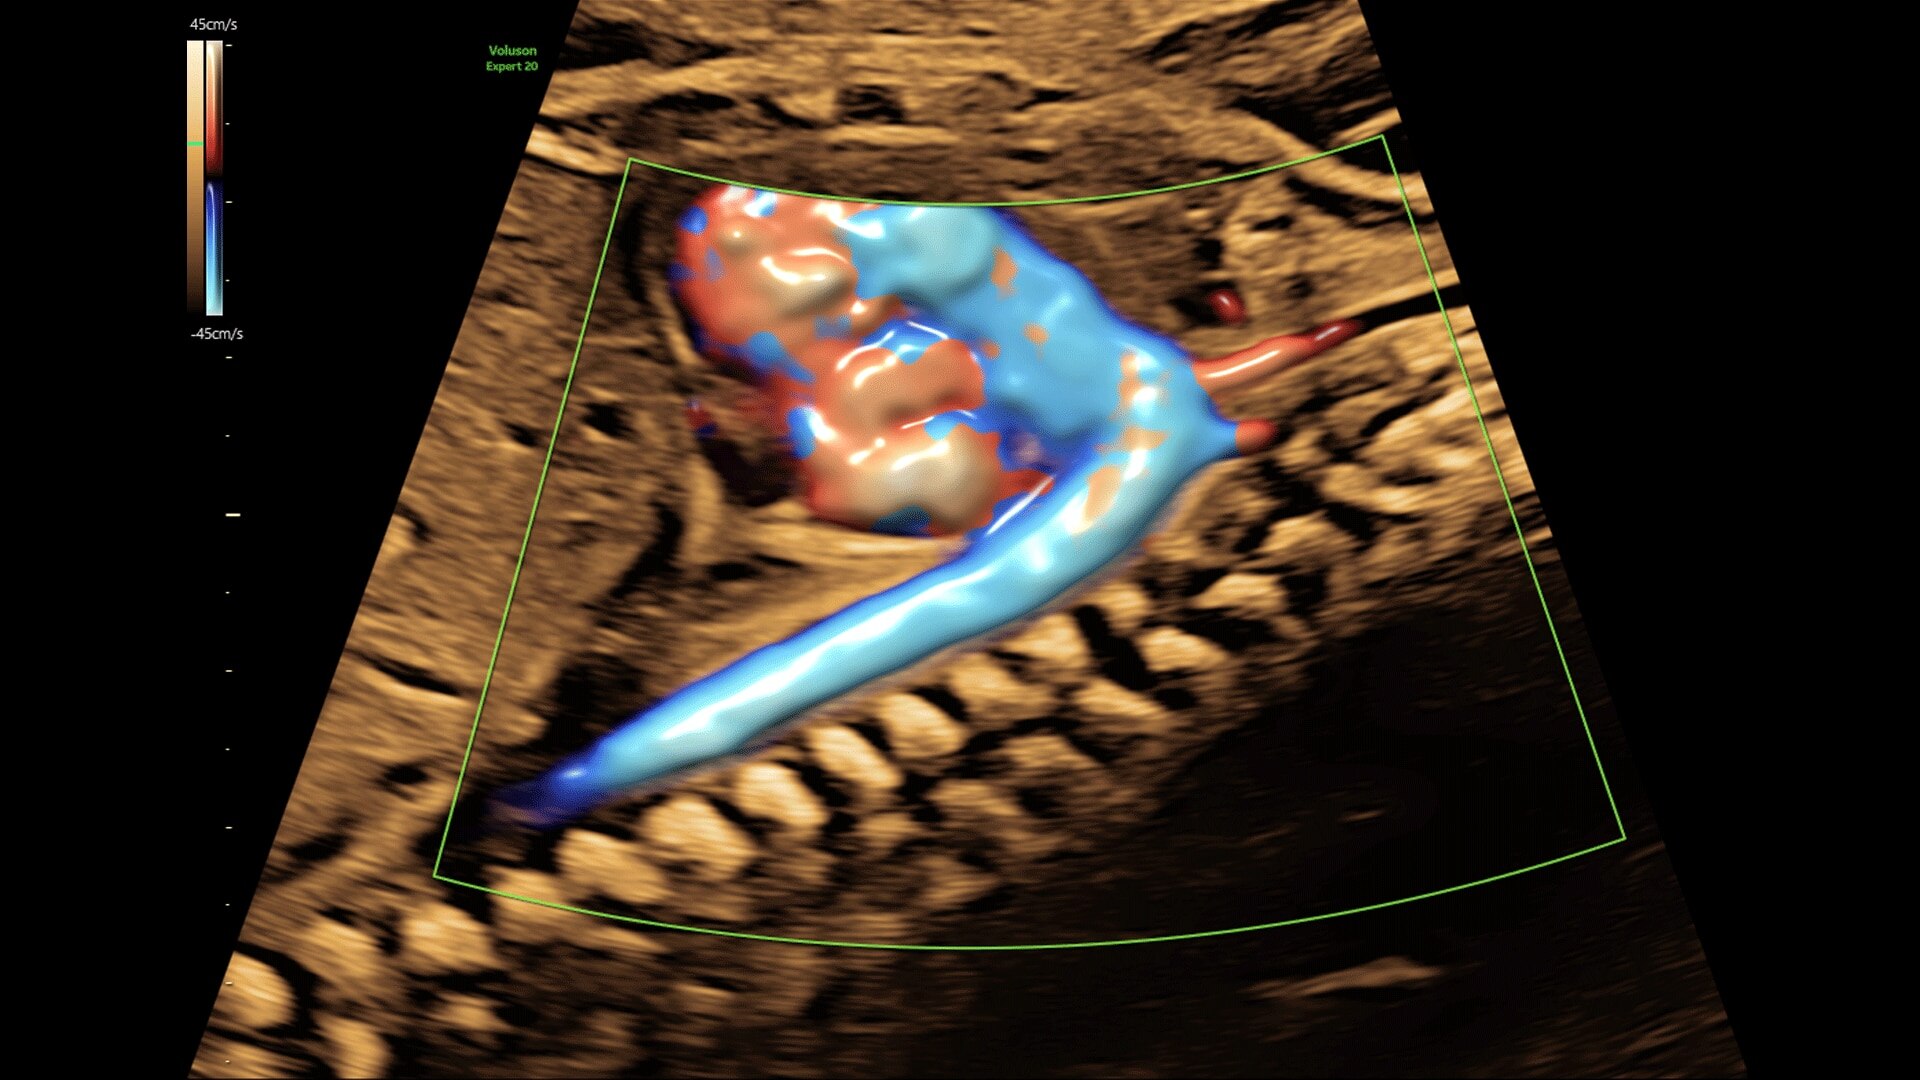

Generate spectacular 2D/3D and color Doppler images with increased penetration and stunning clarity, to help visualize critical details needed for diagnostic assurance. The Lyric Architecture unlocks new imaging and processing power to expand your imaging capabilities for years to come